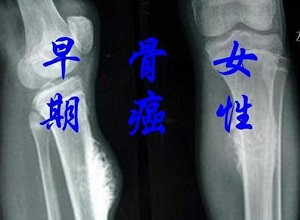

郑州治疗骨癌哪个医馆好:骨癌产生的原因?骨癌虽然在生活中很常见,但还是有很多人对骨癌了解不多。骨癌对患者的危害很大,所以我们应该关注骨癌,从根本上预防骨癌的发生。那么,诱发骨癌的因素是什么呢?让我们来看看郑州御和堂中医师详细介绍:

骨癌的病因是什么?以下是关于骨癌的病因介绍:

骨癌的个原因是物理因素:这种骨癌的病因是指所有的电离辐射,如X射线、氢、放射性同位素等。通过体内或体外辐射会诱发骨癌的发生。过度放疗也可以促进骨肉瘤的出现。临床上称为放射后骨肉瘤。